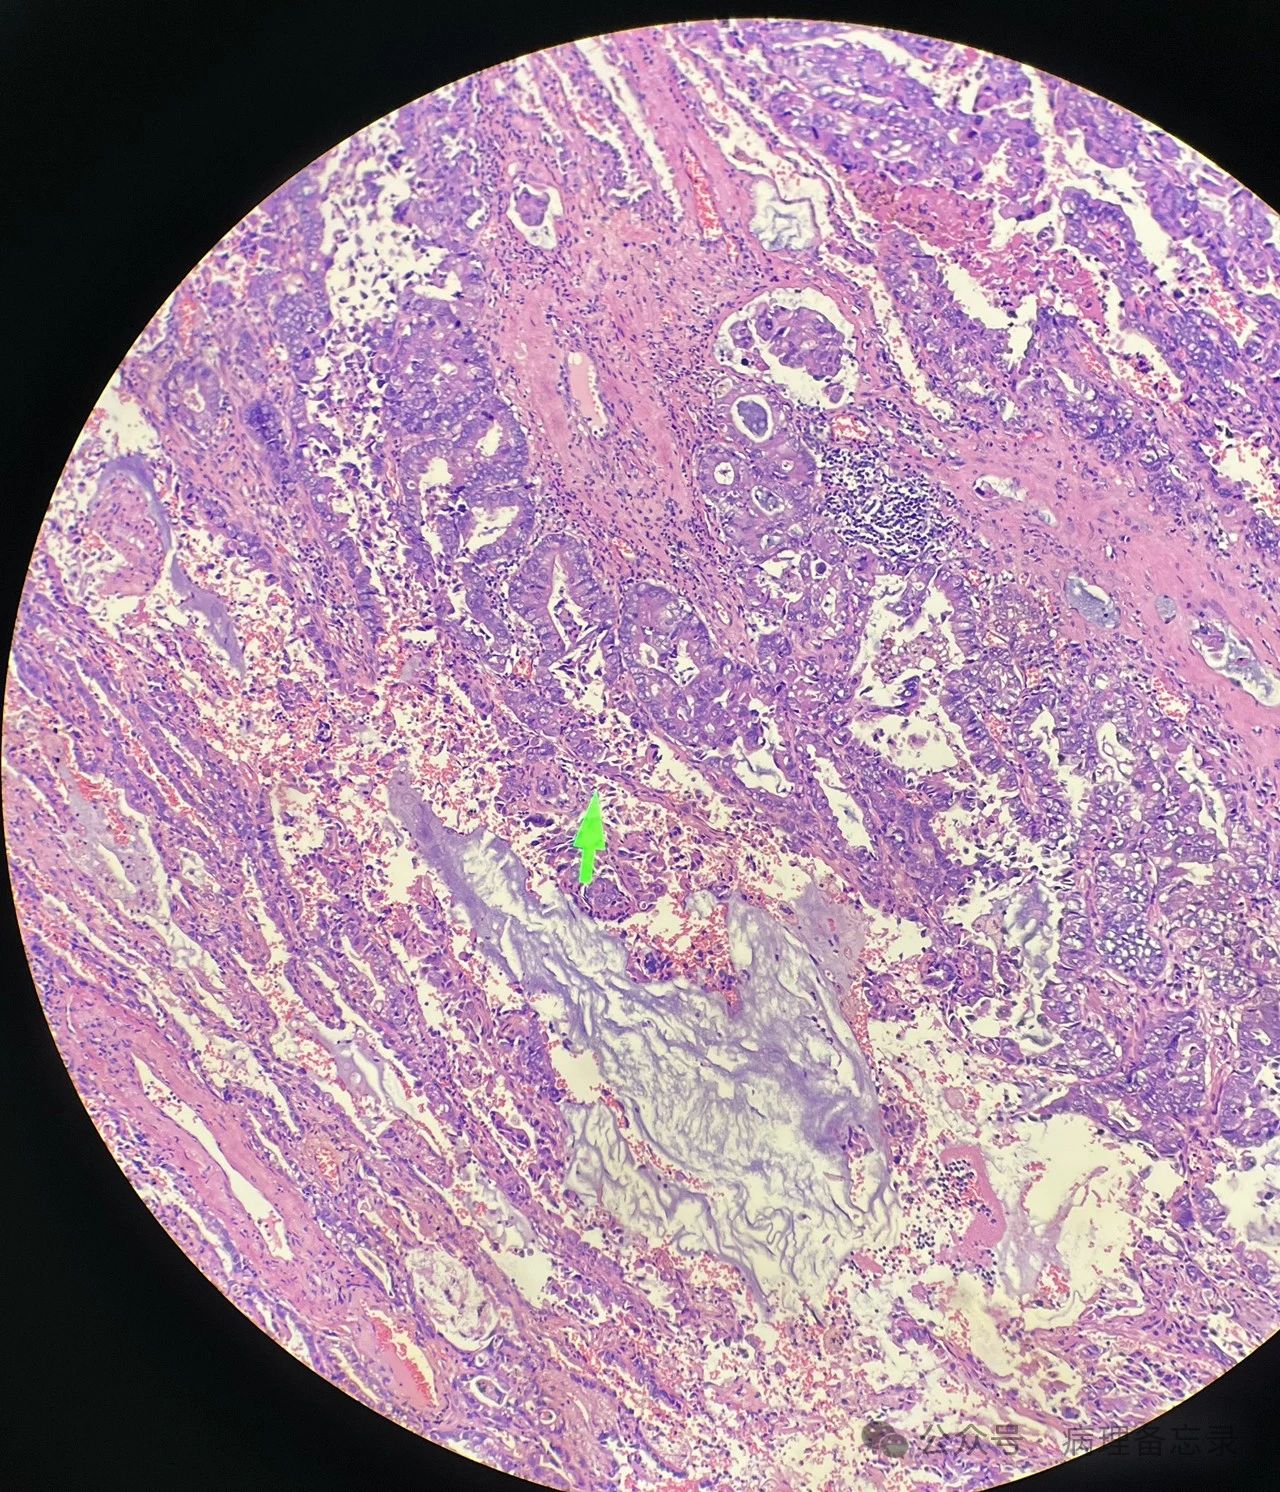

贴壁为主,浸润成分≤5mm(黑色:贴壁型    红色:腺泡型)

腺泡型,肿瘤浸润间质有促纤维反应